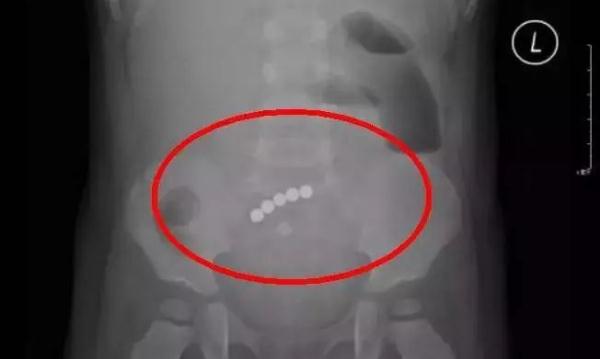

1 巴克球(磁力珠)

巴克球,是一种带有强磁性的金属实心小圆球。

但是,这种巴克球又小又滑,很容易被宝宝误吞。

一旦误吞分分钟是要命的事情——

△2017年11月,深圳一名小男孩因吞入5颗磁力珠,导致肠壁坏死,肠管3处穿孔,且有严重感染。经过三个小时的开腹手术,才被从鬼门关拉回来。